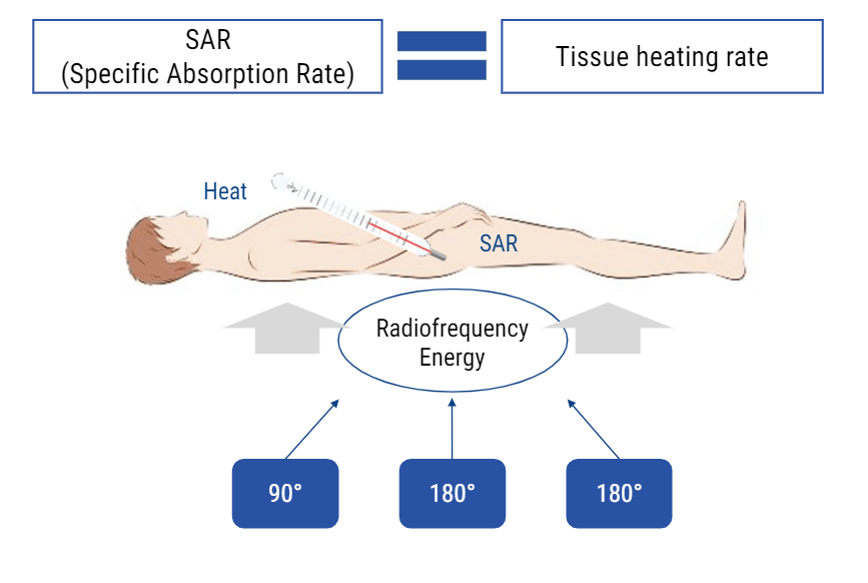

MR and RF Effects on Vitals

MRI and Radiofrequencies can have some biological effects. One that we talked about briefly is the transfer of energy. This occurs in the form of heat. One of the numbers we watch during an MRI exam is the SAR level or specific absorption rate. The rate at which the body is absorbing that heat. If the body absorbs heat, the temperature of the body will rise. SAR is given in watts per kilogram. A SAR level of 4 is considered the uppermost limit during an MRI scan. We can adjust parameters to help keep SAR levels low.